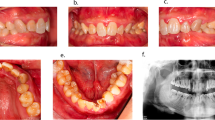

The distinction of some particular forms of periapical area, involving diseases from regular periapical disease, is a matter of considerable importance when choosing a correct treatment. The aim of this study is to describe the differential diagnosis of periapical diseases from six rare cases in clinical practice. The six rare cases are examples of situations where it is difficult to make a differential diagnosis in clinical practice. By retrospective surveys on the clinical examination, radiographs and pathological results, six patients referred to endodontic treatment in our department were analyzed for the accuracy of diagnosis and therapy. The pathoses of the six cases included two atypical radical cysts, periapical cemental dysplasia, cemento‐ossifying fibroma, thymus cancer metastasis in the periapical site and tuberculosis. This report indicates that endodontists should be cognizant of a few particular circumstances when clinically treating periapical diseases.